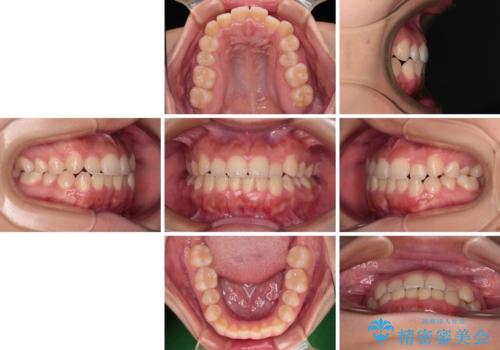

前歯のクロスバイトを改善 インビザライン・モデレートによる矯正治療

- 上下前歯のクロスバイトと叢生を気にして来院された患者様です。

インビザラインでの治療を希望されていて、デコボコの程度が中等度であり、安価なパッケージにて対応可能と判断されたため、インビザライン・モデレートを用いて矯正治療を行うこととしました。

モデレートパッケージは、アライナー数や期限に制約がある一方、安価に治療を行うことができるパッケージです。

アライナー数が制約数内に収まるかどうかはシミュレーションを作成するまで不明なため、すべての方に適用されるものではありません。